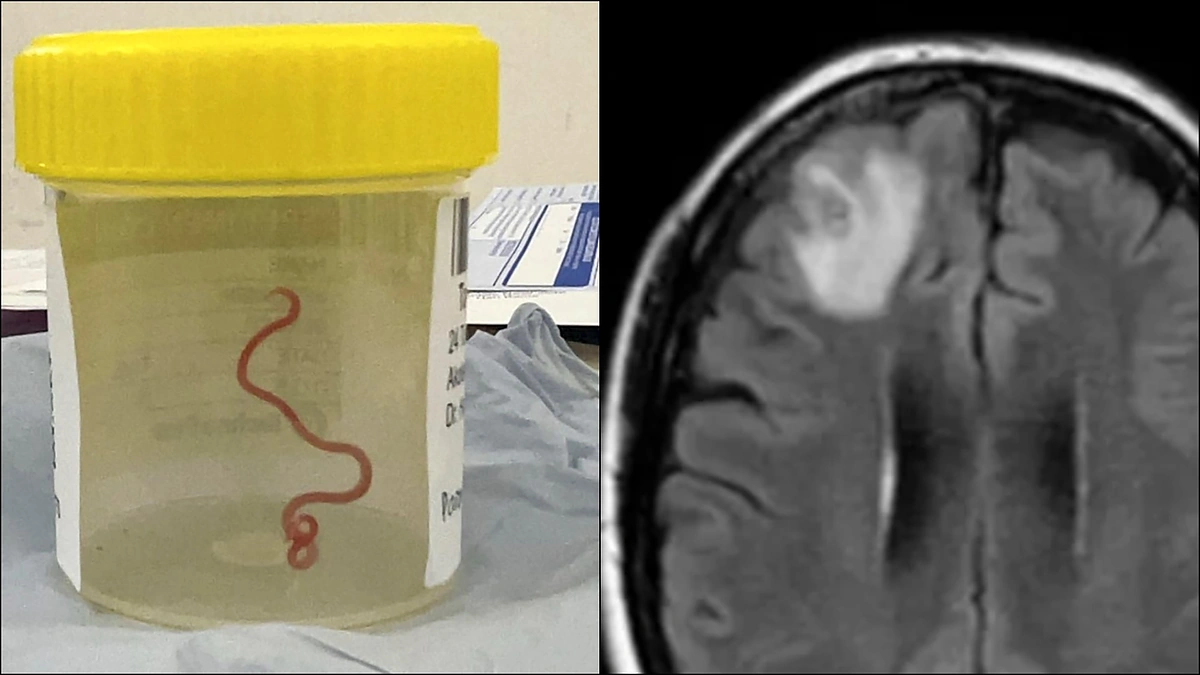

Skelbiama, kad praėjusiais metais vykusios operacijos metu iš pacientės pažeistos kaktinės smegenų skilties (lot. Lobus frontalis) buvo ištrauktas į virvę panašus raudonas parazitas, kuris čia prabuvo bent iki dviejų mėnesių.

„Kiekvienas operacinėje buvęs žmogus patyrė tikrą šoką, kai [chirurgas] paėmė žnyples, norėdamas paimti anomaliją, ir paaiškėjo, kad tai buvo gyvas 8 cm ilgio šviesiai raudonas kirminas“, – BBC sakė Kanberos ligoninės infekcinių ligų gydytojas Sanjaya Senanayake.